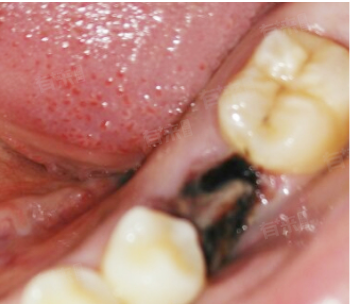

- 干槽症一般发生在拔牙后的3-4天,这是由拔牙创口的感染或血块形成不良导致的。患者可能会出现拔牙部位的剧烈疼痛,这种疼痛可能放射到同侧的头面部。同时口腔内可能出现臭味,拔牙窝内可能呈现黑色或暗灰色的物质。

- 一旦确诊为干槽症,需要在医生的指导下进行局部清创治疗,包括刮除腐败的肉芽组织、使用双氧水和生理盐水冲洗拔牙窝,并放置碘仿纱条等。治疗周期通常需要2-4周。